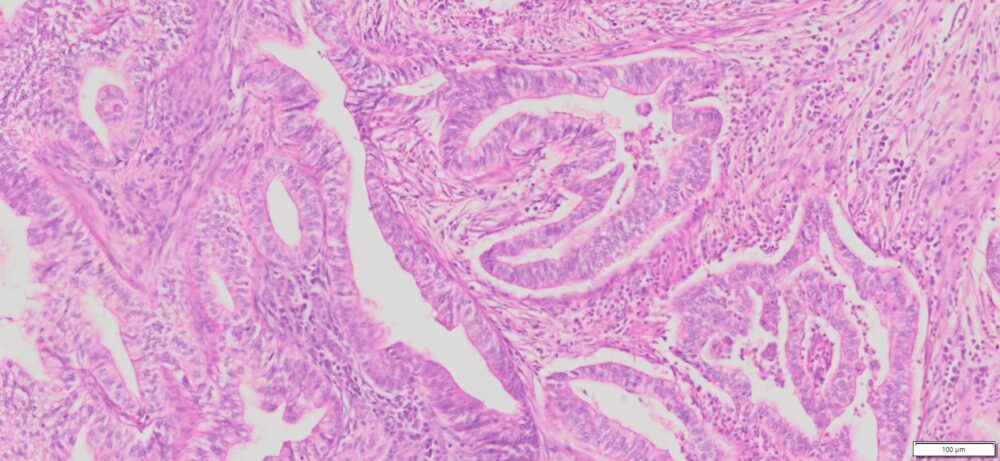

Description

| Tissue | Pathology Diagnosis | Gender/Age (year) | Tissue of Origin | % Tumor area | Tumor Grade | TMN Stage | IHC Data |

| Human Pancreas Cancer | Pancreatic ductal adenocarcinoma | Female/76 | Head of Pancreas | 75% | II | PT2PN1Mx | NA |